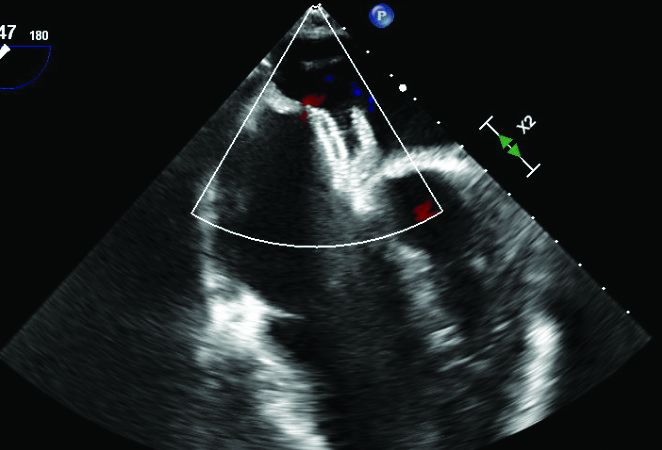

After discussion of treatment options, the patient underwent percutaneous ASD closure with a 20 mm Amplatzer ASD closure device (Abbott Cardiovascular) (Figure 5). Repeat TEE 12 hours after the procedure showed the device seated securely with no residual shunting and mild tricuspid regurgitation. The patient was discharged the following morning with normal right and left filling pressures and prescribed 81 mg aspirin daily. At a 7-week follow up, he was feeling well. Repeat TEE showed a stable ASD closure device without shunting and mild tricuspid regurgitation (Figure 6). His oxygen saturation was 90% on room air. We recommended discontinuing therapeutic phlebotomy and regular follow up with his primary care physician. A repeat hematocrit was not obtained post-operatively due to the patient’s lack of symptoms and continued improvement in oxygen saturation.

Figure 6

Figure 6. Transesophageal echocardiogram at an 8 week follow up. Amplatzer Septal Occluder device is seated well with no shunting across atrial septum.